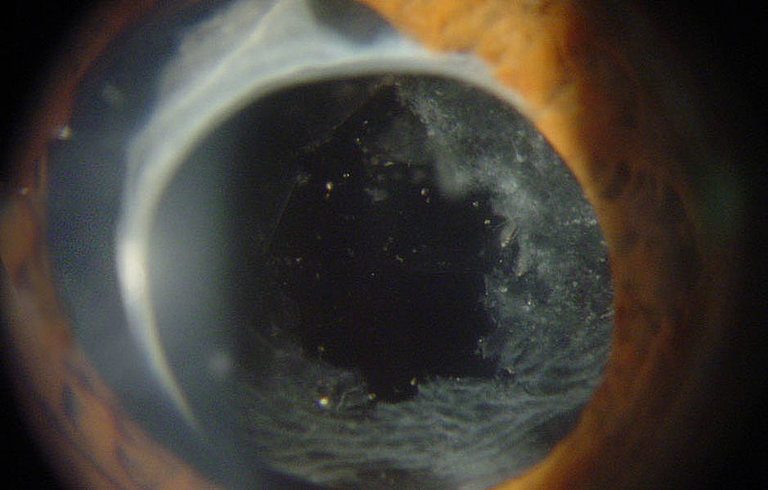

Nach der Grauer Star Operation kann es sein, dass die Sehleistung langsam wieder nachlässt und Sie als Patient erneut einen Schleier bemerken. Der Grund hierfür ist oft eine Trübung der alten körpereigenen Linsenhinterkapsel. Diese Trübung wird als Nachstar bezeichnet und Sie können es sich als getrübtes dünnes Häutchen hinter Ihrer Kunstlinse vorstellen.

Zunächst wird die Pupille mit Augentropfen weitgestellt und das Auge mit einem Augentropfen betäubt. Danach wird ein Kontaktglas auf das Auge aufgesetzt. Der Laser ist an eine Spaltlampe angeschlossen. Durch das Kontaktglas sieht Ihr Augenarzt die eingetrübte Linsenhinterkapsel vergrößert und richtet den Laserstrahl direkt auf das dünne Häutchen. Wenn der Laser ausgelöst wird, entstehen in dem Häutchen kleine Löcher. Auf diese Weise wird der zentrale Teil der Nachstarmembran eröffnet und das Licht kann wieder ohne Hindernis ins Auge gelangen. Nach erfolgreicher Laserbehandlung tritt in der Regel kein erneuter Nachstar mehr auf.